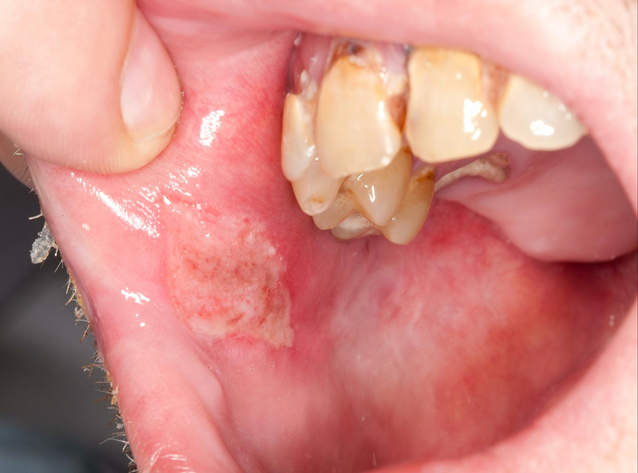

Tongue ulcer due to vit B deff. with angular cheilitis

3. Nutritional Deficiencies

Sometimes, what’s missing from your diet can show up in your mouth. A lack of key nutrients is a common cause of recurrent oral ulcers. Specifically, deficiencies in:

- Vitamin B12

- Iron

- Folic Acid